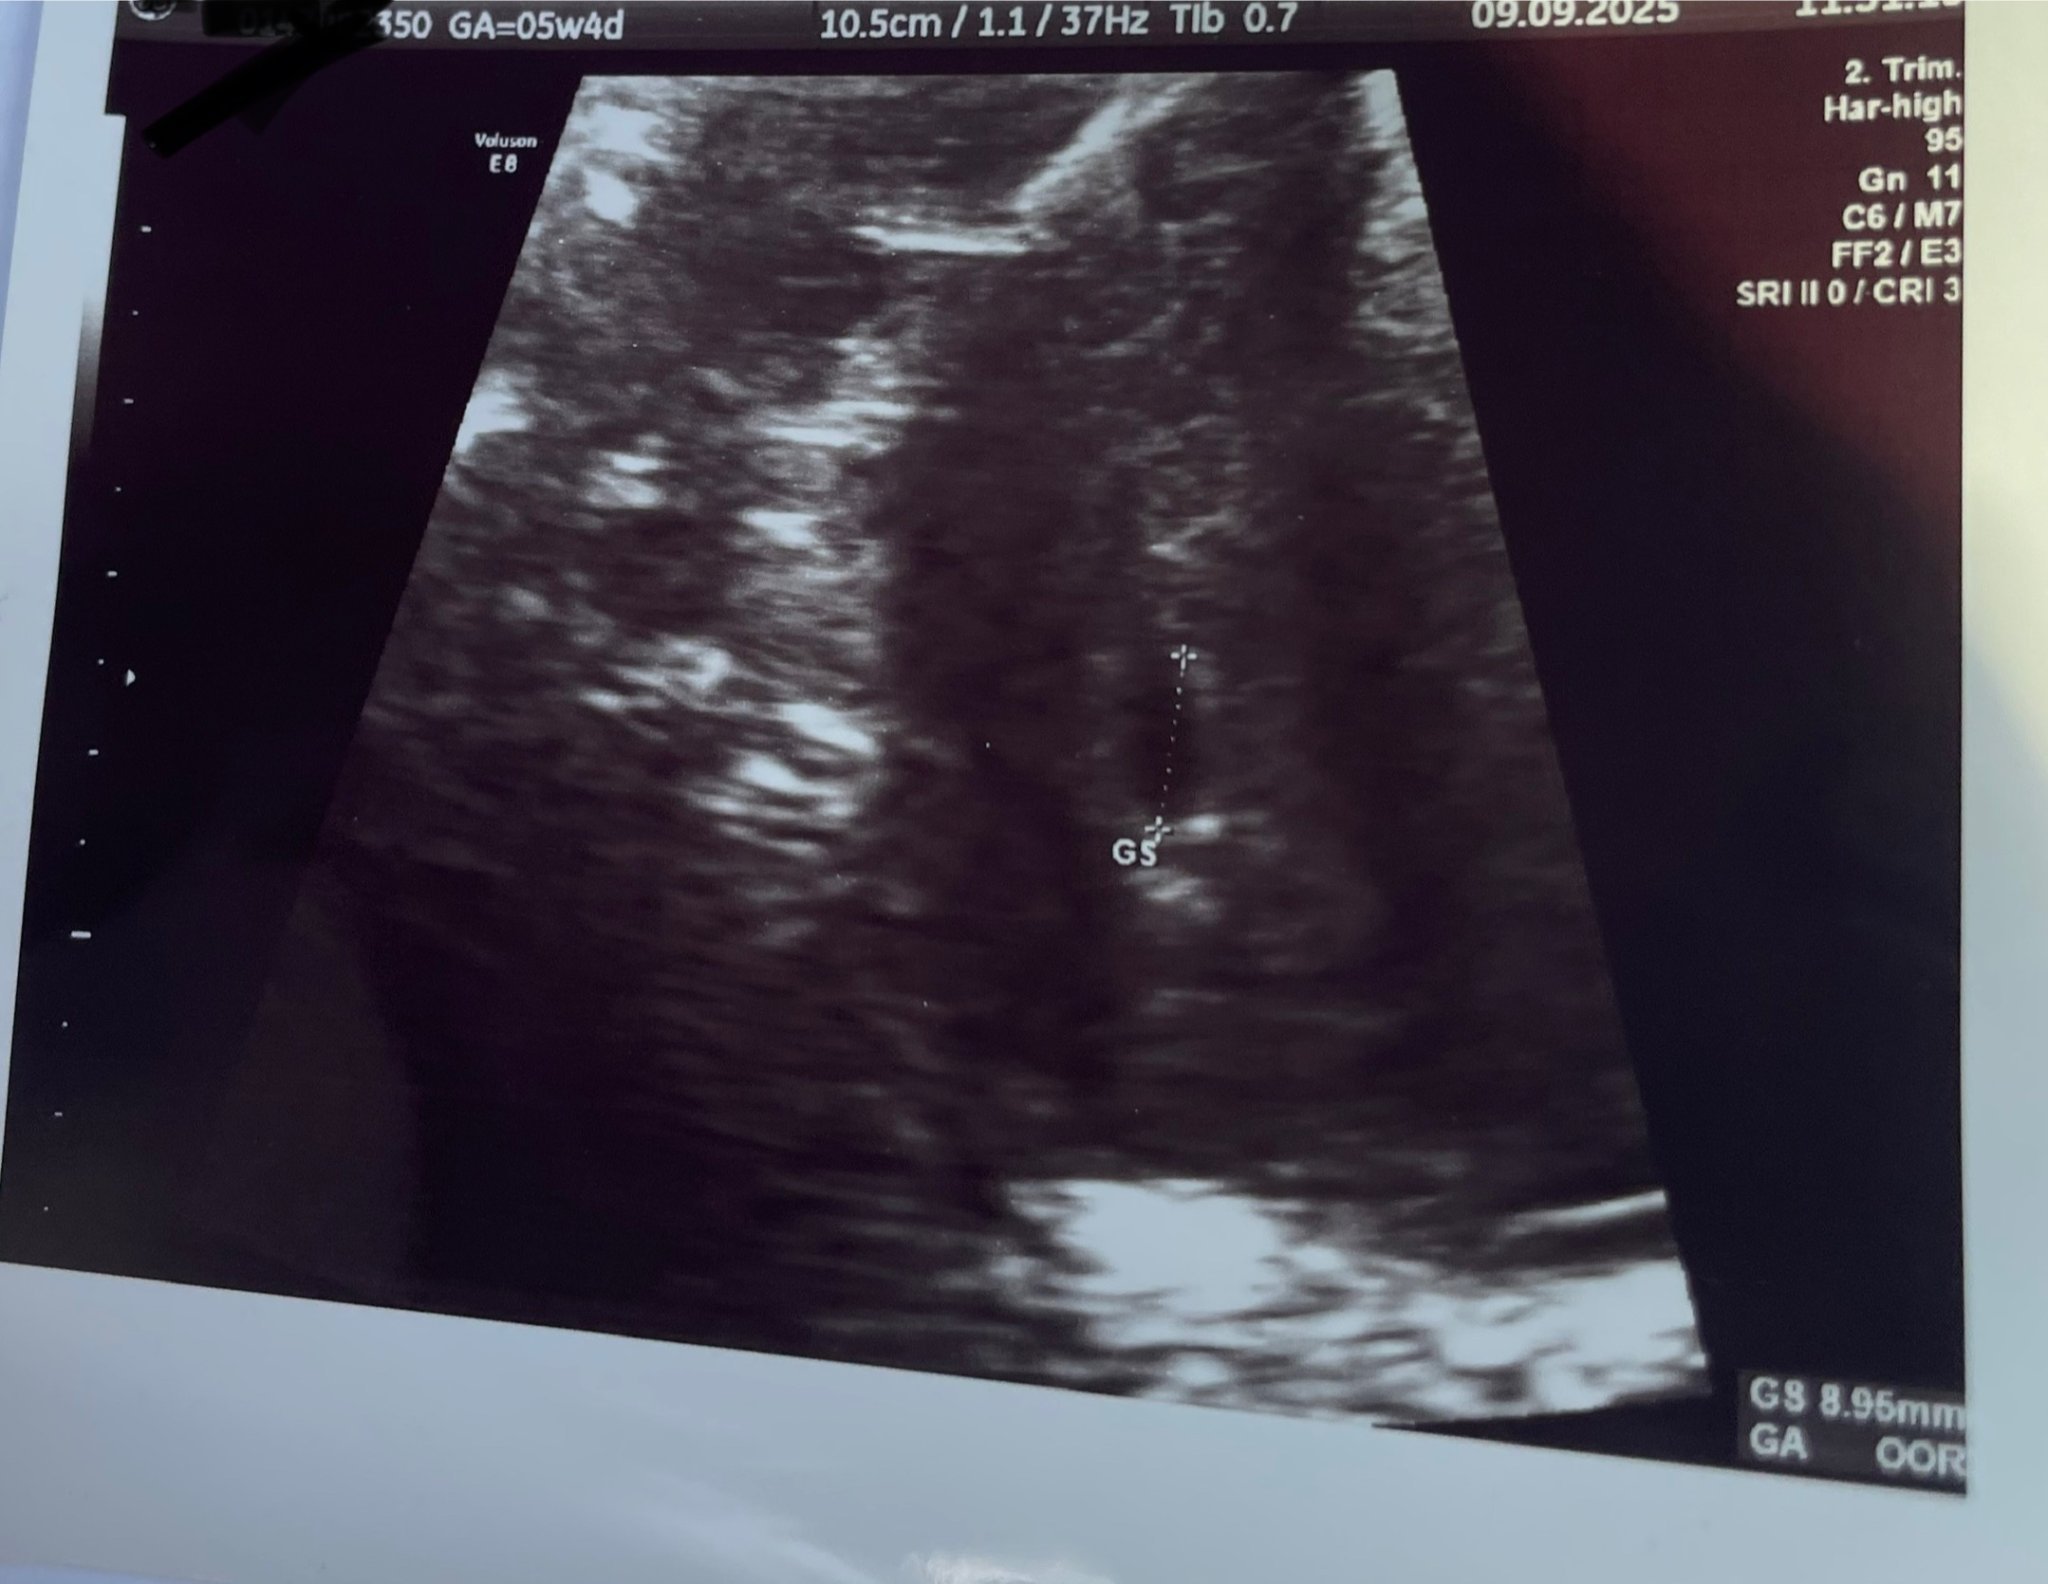

Здравейте! Днес бях на преглед и според последния цикъл съм в 5гс +4. Бихме ли ми казали дали е нормално да не се види самият плод. Това е снимката, с която се сдобих, а според лекарят отбелязаното е плоден сак. Вика ме след 2 седмици отново.